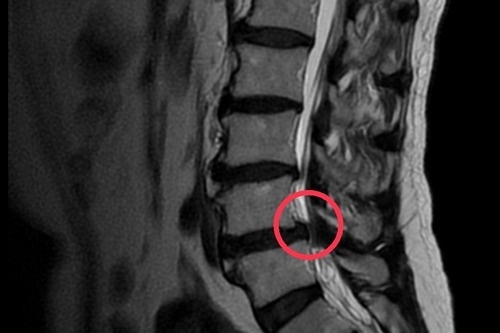

左圖、右圖:磁振造影顯示黃先生腰椎滑脫,神經受到壓迫。